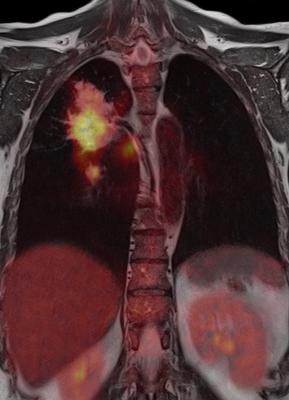

PET imaging often is used to assess tumor glucose metabolism and an essential tool for lung cancer management. Studies have shown that some of the biological and genetic variations within tumors potentially can be captured in PET images.

Using big data radiomics — extracting comprehensive information from PET images — researchers evaluated the associations between radiomic features of tumors and EGFR and KRAS mutations in about 350 NSCLC lung cancer patients. The mutations were confirmed by molecular testing based on biopsies of tumor tissues, the standard of care for mutation identification. Researchers found that radiomic features describing different aspects of the tumor, such as its shape and textures, appear to be associated with EGFR mutations. Their results suggest that different metabolic imaging patterns (or imaging phenotypes) that are quantified by radiomic features may be caused by EGFR mutations.